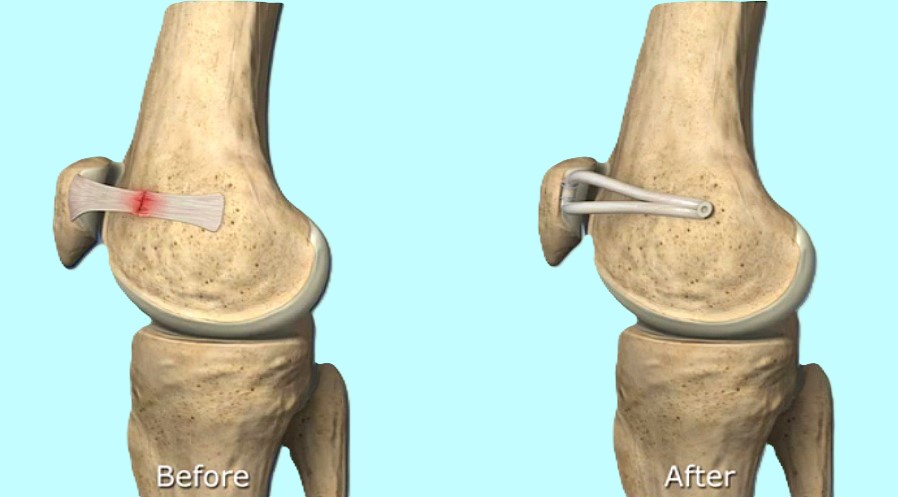

膝蓋骨脱臼手術 /MPFL再建術

内側膝蓋大腿靱帯(MPFL)再建術

横浜整形外科野村院長は世界で最も早く膝蓋骨脱臼に対するMPFL再建術を開発し現在まで500例以上の手術を行ってきました。この数は世界トップクラスです。

再建材料として1997年まで人工靭帯法、1998年に自家腱法を開発しました。手術結果は世界的雑誌 The Knee、Arthroscopy、AJSMに4つ論文が掲載されました。採取する腱の半腱様筋腱や薄筋腱は採取しても運動機能に影響はありません。人工靱帯法でも組織学的に良好な靱帯が再生されることが判明しています。世界的雑誌AJSMのレビュー(Bucken 2010,AJSM)ではMPFL再建術の2009年以前の世界の論文から信頼できる論文は12個のみであり、その内野村医師は2000年に世界で最初に信頼できる論文を発表したと記載されています。12個の内3個の野村医師の論文が選ばれています

2022年最新手術法開発

術後スケジュールは手術2~4日目に杖なしで退院・術後リハビリ通院不要・ランニング2ヶ月~、スポーツ3ヶ月~。世界で最も早いリハビリを達成。